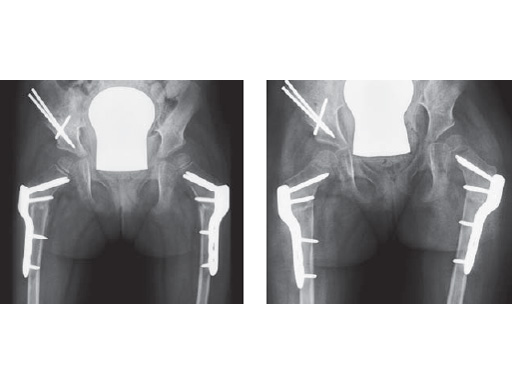

Intraoperative x-ray

Fig. 3-4

Postoperative x-ray with planned correction

Fig. 1-2